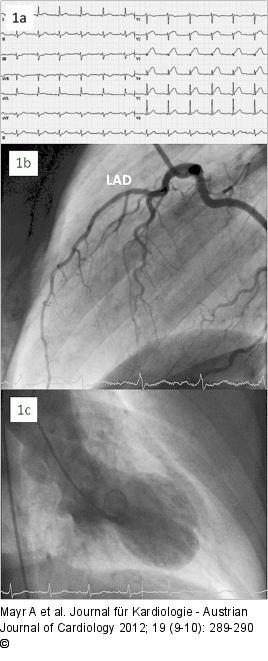

Abbildung 1a-c: STEMI 1. (a): Initial ECG showing anterior STEMI; (b): First coronary angiography showing no obstruction/stenosis of the left descending coronary artery (LAD). Right coronary artery and circumflex artery also showed no abnormalities; (c): Global left ventricular function was reduced moderately with anterolateral, apical as well as inferior hypokinesis. |

1. (a): Initial ECG showing anterior STEMI; (b): First coronary angiography showing no obstruction/stenosis of the left descending coronary artery (LAD). Right coronary artery and circumflex artery also showed no abnormalities; (c): Global left ventricular function was reduced moderately with anterolateral, apical as well as inferior hypokinesis. |